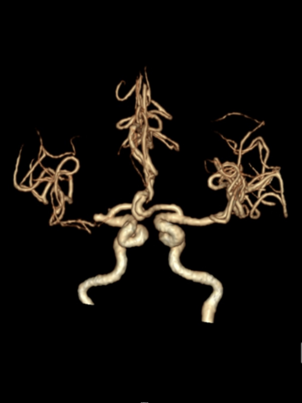

3D造影

动脉长鞘怎么置入一技之“长”丨经桡及经股困难入路应用赛诺神畅APEX TRA GC™导引导管建立通路病例合集_https://www.jmylbn.com_新闻资讯_第38张

病变血管放大造影

后撤微导管至右侧大脑中动脉M1段分叉处,路图下微导丝超选入右侧大脑中动脉M2段上干,跟进微导管,撤出微导丝,手推造影显示微导管在血管真腔内,再次送入微导丝,撤出微导管,沿微导丝送入2.0*15mm 球囊扩张导管,由远及近分次进行扩张,扩张后显示狭窄段较前明显好转。

撤出微导丝,沿球囊扩张导管送入4.5*14mm 支架,精确定位后缓慢释放支架。

术后情况

支架植入后造影提示残余狭窄约0%, 右侧大脑中动脉供血区供血较前明显改善,前向血流达到3级。患者麻醉复苏后无不适,恢复良好出院,继续双联抗血小板聚集及他汀类药物治疗。

术后即刻复查头CT提示:支架张开良好无造影剂渗漏。